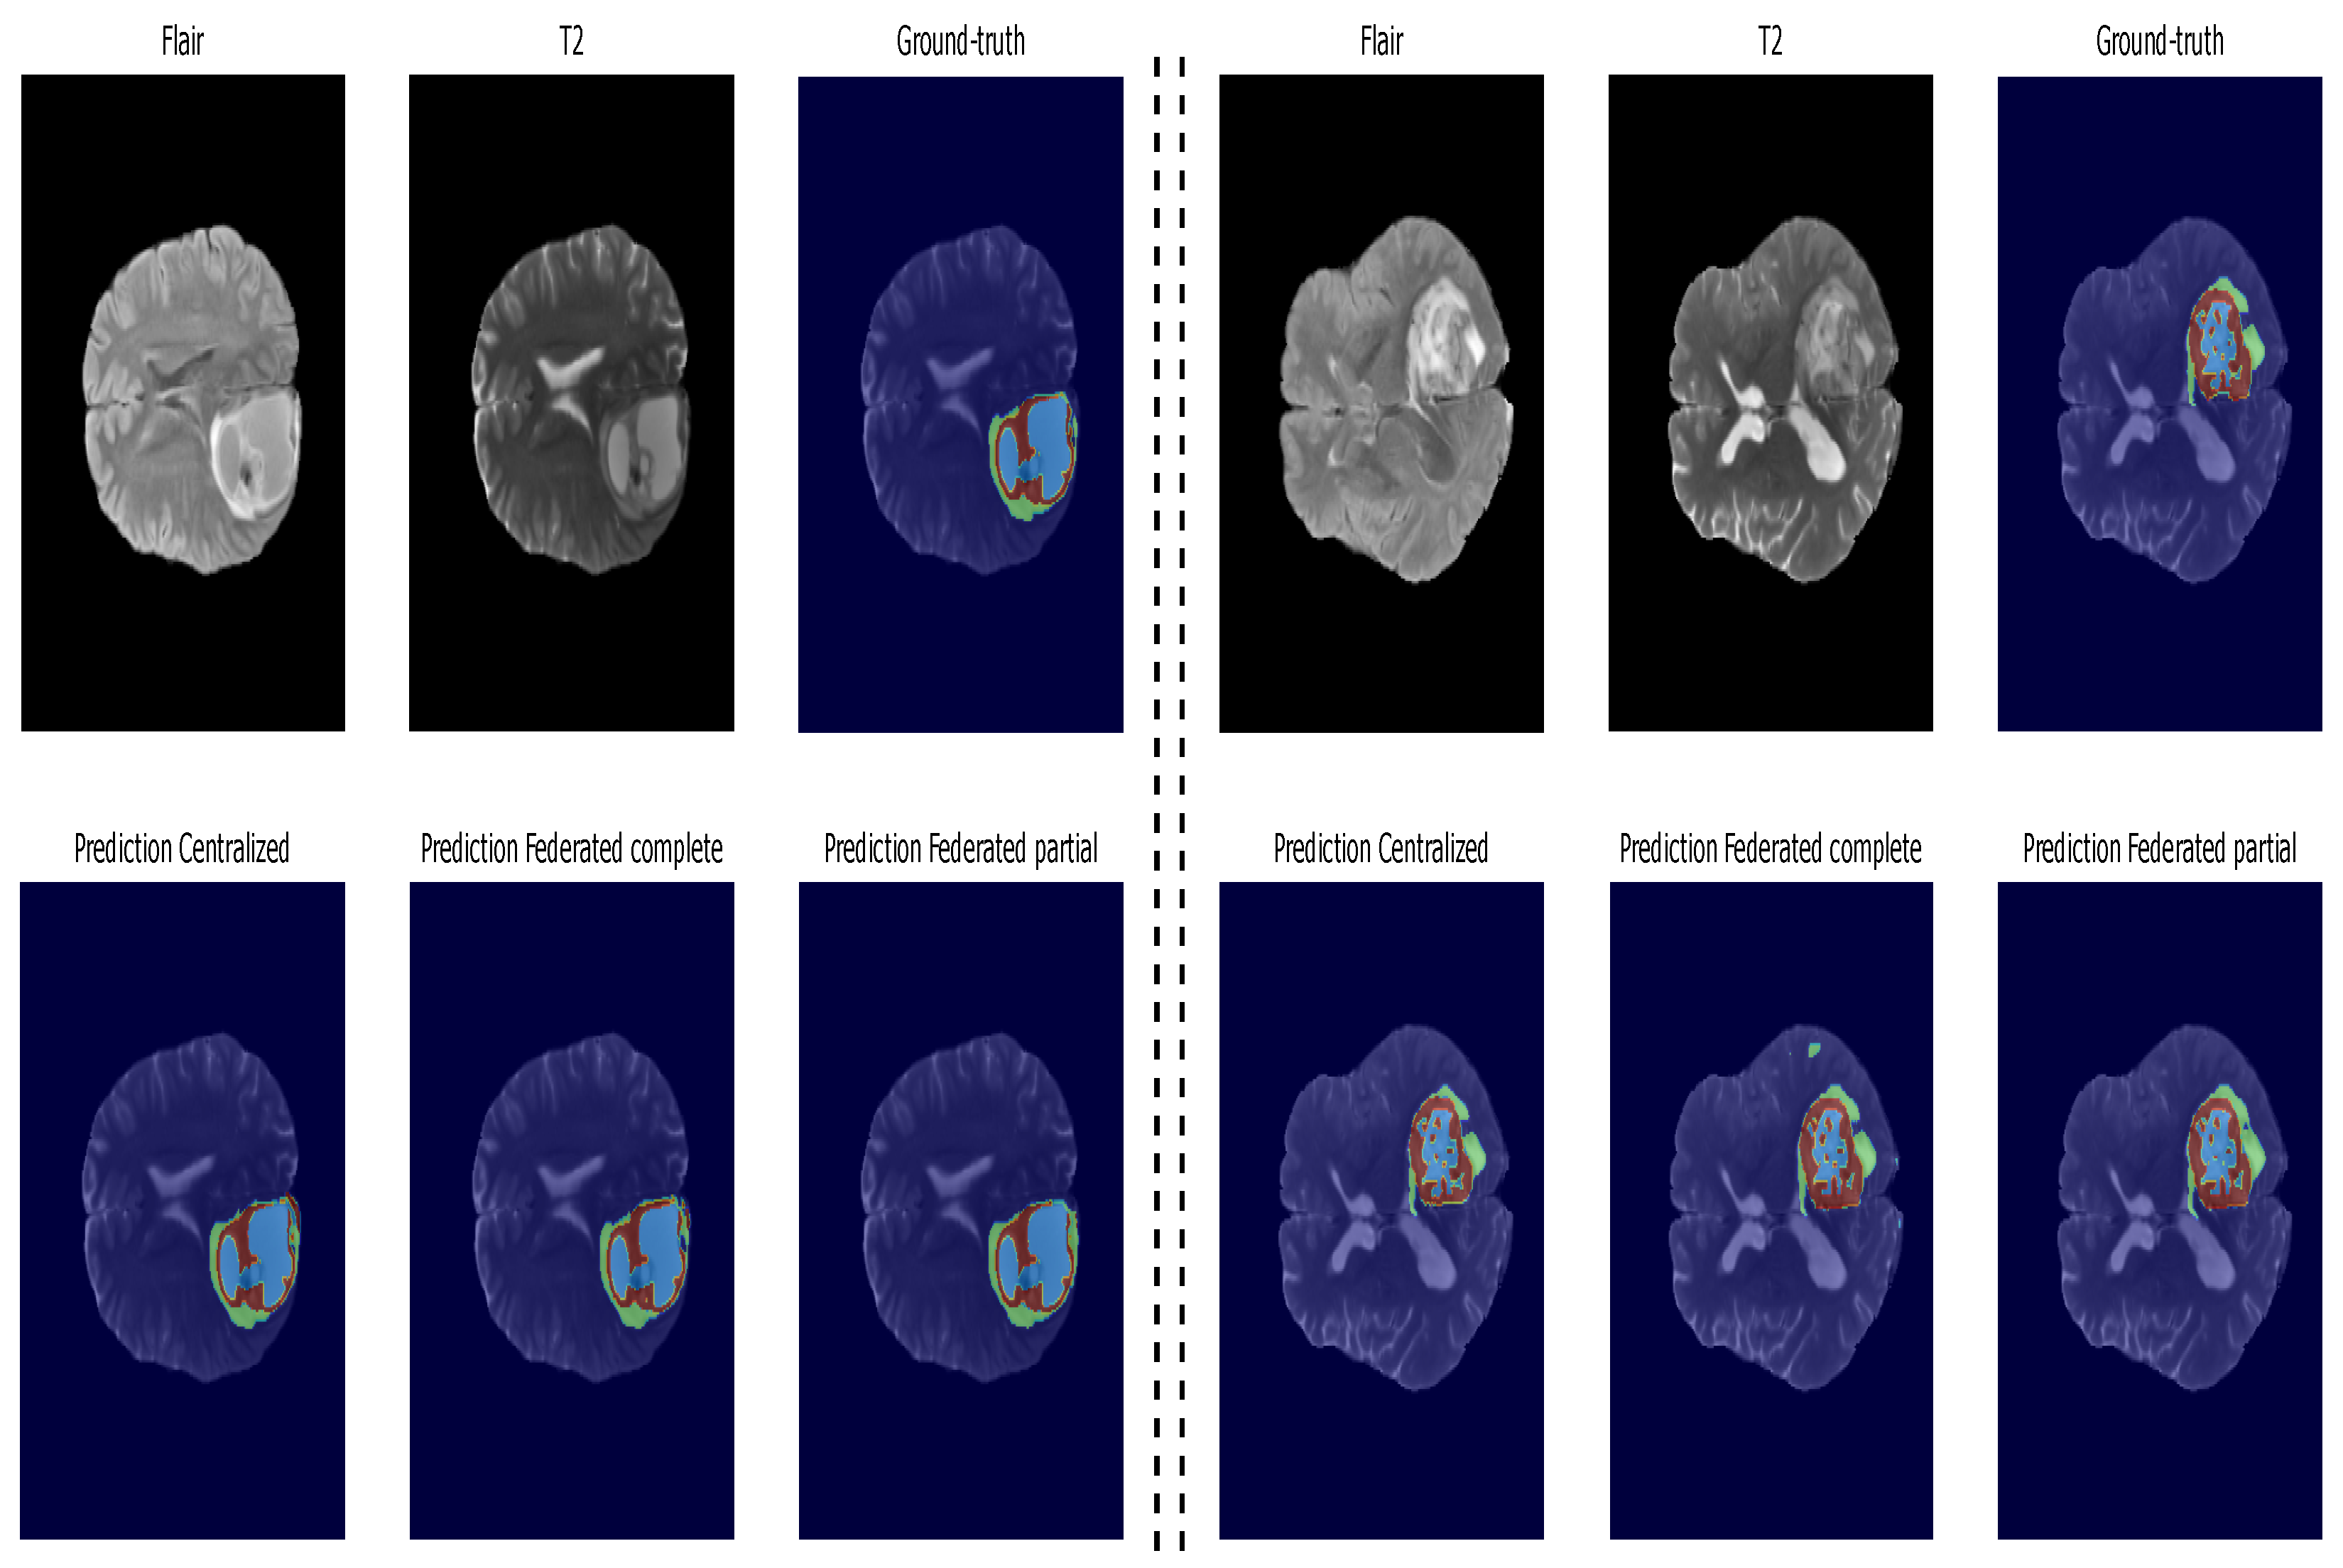

5.2. Second Step of Validation: Whole-Image Validation

5.3. Inference: Testing on Unseen Data